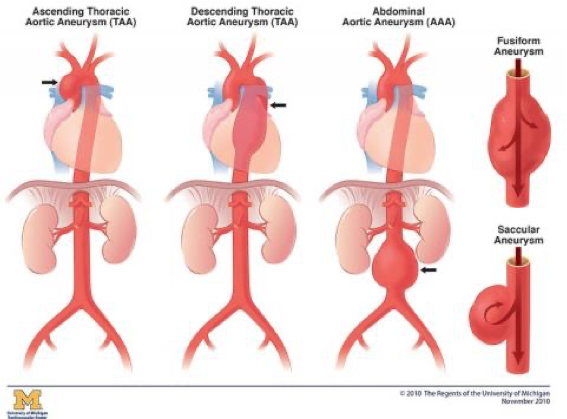

What does this refer to

Abdominal (aortic aneurysm) (AAA)

Thoracic

Ascending (aorta)

Aortic arch

Descending (aorta)

Most Common types of Aortic Aneurysms

What does this refer to

Re

What aneurysm shape is the following

bulging on one side

Saccular

What aneurysm shape is the following

Bulging on all sides

Fusiform